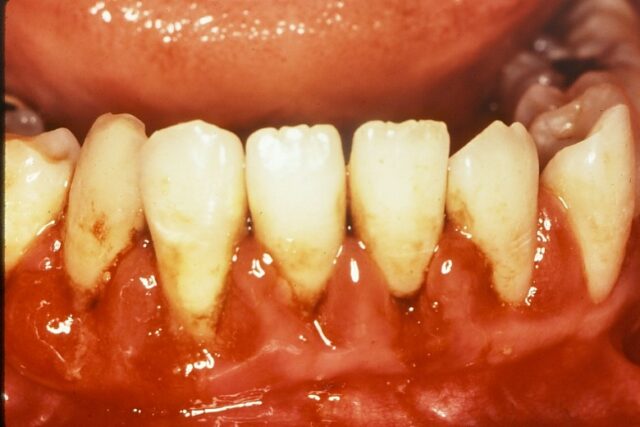

歯周病では炎症にともなって、その材料や細菌が増えますので、VSCが増量します。

しかも、歯周病ではメチオニンというアミノ酸から作られるメチルメルカプタンというVSCが多く、腐った玉ねぎのような非常に強い悪臭を持っているのが特徴です。